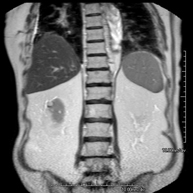

- RM Abdomen

Prueba diagnóstica no invasiva que consiste en la obtención de imágenes de alta definición anatómica del abdomen mediante el empleo de un campo electromagnético y ondas de radio (con un emisor y un receptor). No utiliza radiación ionizante. En esta exploración se incluyen el hígado, páncreas, bazo, vía biliar, vesícula biliar,Entero-RM glándulas suprarrenales, riñones, aorta abdominal, vena cava inferior, estómago, duodeno,…En ocasiones se deberá emplear contraste paramagnético (Gadolinio) para caracterizar las lesiones.

- RM Riñones

Prueba diagnóstica no invasiva que consiste en la obtención de imágenes de alta definición anatómica de ambos riñones mediante el empleo de un campo electromagnético y ondas de radio (con un emisor y un receptor). No utiliza radiación ionizante. Se realiza para estudiar cualquier lesión localizada en ambos riñones. Normalmente se requiere el uso de contraste paramagnético (Gadolinio) para caracterizar las lesiones.